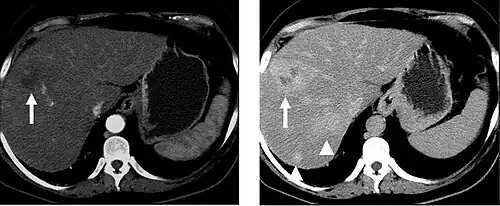

Portal venous phase

The most common technique is to perform portal venous phase imaging in the abdomen and pelvis (approximately 60–90 seconds after contrast administration, figure 2). This results in near optimal contrast opacification of the majority of the solid abdominal organs and it is used for a wide variety of indications: nonspecific abdominal pain; hernia; infection; masses (with a few exceptions such as hypervascular, renal, and some hepatic tumors); and in most follow-up examinations. As a general rule, this single phase is adequate unless there is a specific clinical indication that has been shown to benefit from other phases.

FIGURE 2. Contrast enhanced CT demonstrating parenchymal enhancement of the intra-abdominal organs in the portal venous phase (axial left, coronal reformat right).